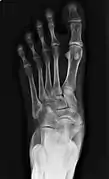

Radiological images

From left to right: Type 1, 2 and 3